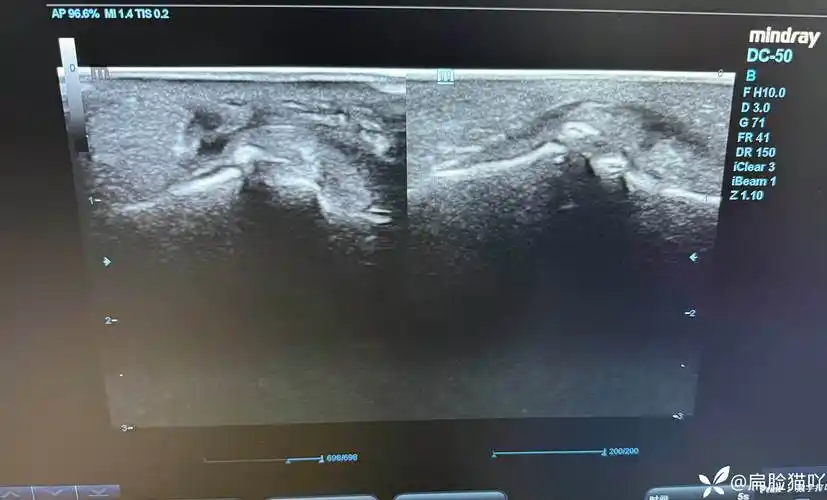

规培笔记我用超声看到了世卫组织扬言要消灭的肿瘤

手指异物超声

iga肾病肾脏的超声图像(肾穿刺活检确诊)